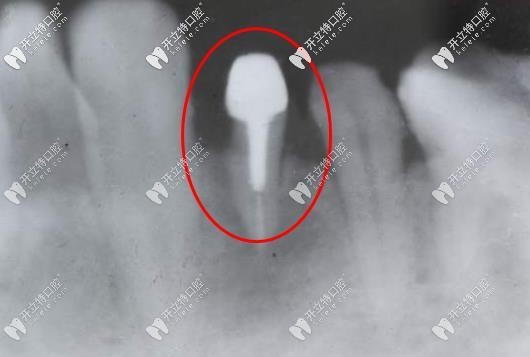

打樁后的牙片

牙齒打樁就是插入根管內(nèi)的部分,用摩擦力和粘固力、粘結(jié)力獲得固位,然后為修復(fù)體提供牢固的基礎(chǔ),主要是用于患者牙齒缺損較大或者因為外傷只剩下牙根的情況,剩下的牙根太短,不能直接用修復(fù)體修復(fù),這個時候就用到了打樁,去加固并延長折斷的牙齒。

牙齒打樁的材料整體分為纖維樁和金屬樁兩大類,其中金屬樁又分為不銹鋼、金鈀合金、金鉑合金等種類。